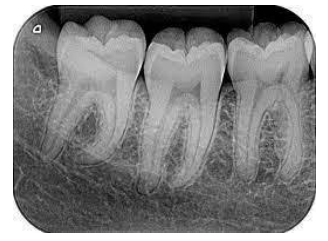

Para uma correta montagem das radiografias dentárias, o profissional deve possuir conhecimento do tipo de exame executado e dos elementos dentários presentes.

Diante disso, analise a radiografia a seguir:

Essa é uma radiografia do tipo: